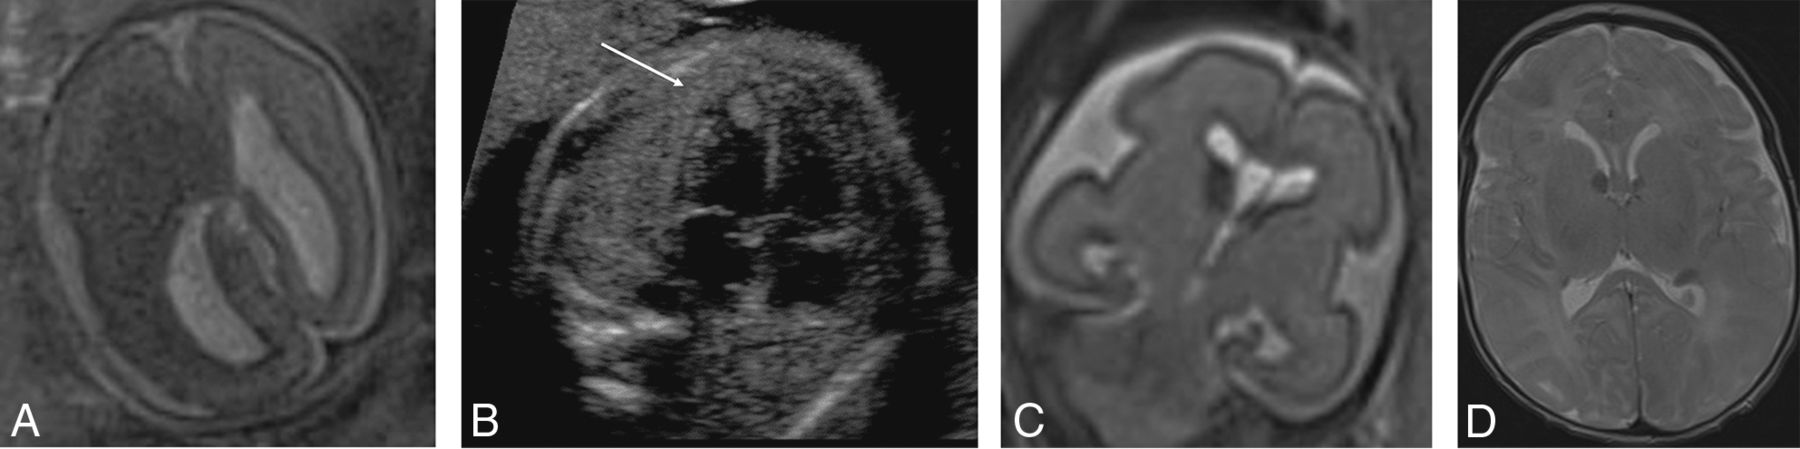

Subjects 1–8 had fronto-occipital head dimension measurements of ≥2 SDs greater than the mean. Of 5 cases with genetic testing, an MTOR or PI3KCA mutation was identified in 3, with megalencephaly, polymicrogyria, polydactyly, and hydrocephalus syndrome diagnosed prenatally in case 2 because of sonographically demonstrated postaxial polydactyly (Figs 1 and 2). Tuberous sclerosis was confirmed on genetic testing in 2 cases with cardiac rhabdomyoma, and a putative diagnosis was made in a third case with fetal hemimegalencephaly, a markedly enlarged ipsilateral GE, and a cardiac rhabdomyoma (Fig 3). In 2 subjects with large head sizes and no genetic testing, megalencephaly and hemimegalencephaly were present on postnatal imaging.

PIK3CA pathogenic variant. Case 2 at 31 weeks 3 days' gestation. Megalencephaly, polymicrogyria, polydactyly hydrocephalus syndrome due to a PIK3CA heterozygous pathogenic variant. The fronto-occipital diameter is >6 SDs above the mean for gestation. Enlarged bilateral ganglionic eminences (arrows, A) are seen on T2-weighted single-shot FSE and DWI (A and B). Diffusion-weighted b = 0 image (C) and T2*-weighted EPI (D) confirm the absence of hemorrhage as the cause for ganglionic eminence enlargement. Abnormal opercularization is present with Sylvian fissures lined by peri-Sylvian polymicrogyria (E). Postaxial polydactyly is seen on sonography with arrow indicating a rudimentary sixth digit medial to the fifth digit of the hand (F).

MTOR/PROS pathway mutations. Smith-Kingsmore syndrome (case 5) at 25 weeks' gestation demonstrates enlarged GEs on DWI and T2-weighted single-shot FSE. There is bilateral underopercularization and left peri-Sylvian polymicrogyria (arrow). The right hemisphere is mildly overgrown.

Tuberous sclerosis complex (A and B). Case 1. Dichorionic diamniotic twin at 22 weeks 5 days' gestation. T2-weighted single-shot FSE image demonstrates hemimegalencephaly and marked enlargement of the ipsilateral GE, which merges with a hypointense masslike lesion in the enlarged right cerebral hemisphere. The fetus had left ventricular cardiac rhabdomyoma on prenatal sonography (arrow, B); the findings likely represent tuberous sclerosis complex with an associated hemispheric malformation or, less likely, coexistent subependymal giant cell astrocytoma. No postmortem data or confirmatory genetic testing was available. Case 8. T2 single-shot FSE at 25 weeks gestation (C) and T2 FSE at 1-week postnatal imaging (D) demonstrate mild enlargement of the right GE, ipsilateral and mild ventriculomegaly on fetal MR imaging, and typical changes of tuberous sclerosis complex postnatally. The fetus' father also had tuberous sclerosis complex.

Of 12 fetuses with small head sizes, 8 had tubulin mutations and 7 of these were mutations involving the TUBA1A gene; 2 had clinical and imaging findings consistent with Walker-Warburg syndrome and cobblestone lissencephaly postnatally; 1 had a PDHA1 mutation; and 1 had a fetal akinesia dyskinesia sequence (Fig 4).

TUBA1A mutations (A–C). Case 18. T2-weighted single-shot FSE at 24 weeks 4 days' gestation. TUBA1A pathogenic heterozygous variant. The bilateral GEs are enlarged. The fronto-occipital diameter is 2.5, standard deviations below the mean. The corpus callosum and cerebellum are severely hypogenetic/hypoplastic. Underopercularization, severe ventriculomegaly, a thin kinked brainstem (A), a ventral pontine cleft suggestive of a Walker-Warburg phenotype, and apparent diencephalic-mesencephalic fusion or dysplasia (C) are also noted. D, Case 19 at 33 weeks. TUBA1A mutation with enlarged, cavitated GEs and abnormal persistence of hemispheric lamination.

PDHA1 and OPHN1 mutations. A and B, PDHA1 mutation. Case 20 at 23 weeks 3 days' gestation. PDHA1 mutation. Agenesis of the corpus callosum with the anterior commissure present (short arrow), cavitated enlarged GEs, and anterior temporal pole subependymal pseudocysts (germinolytic cysts) (long arrows). C and D, Case 21 at 29 weeks. OPHN1 mutation with mild ventriculomegaly (11 mm) and bilaterally enlarged GEs.